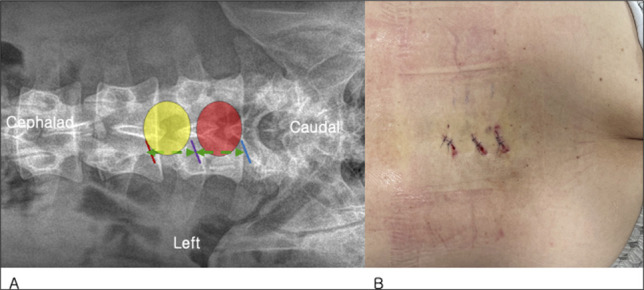

研究设计:回顾性。目的:比较单侧双门静脉内窥镜(UBE)单节段减压与多节段减压治疗退行性腰椎管狭窄无不稳定性的长期临床效果。背景资料总结:单侧双门静脉内窥镜减压已被证明可以有效缓解椎管狭窄而不不稳定。缺乏长期的数据,特别是,使用这种微创技术的单节段和多节段手术之间的比较尚未提出。方法:每组98例患者进行人口统计学倾向匹配。所有患者至少进行了5年的随访。临床结果包括Oswestry残疾指数、视觉模拟系统(VAS)、行走时间、手术时间和住院时间。结果:单节段减压组的Oswestry功能障碍指数由术前的62.98±11.53改善至最后随访时的18.51±8.63 (P < 0.001)。多节段减压从64.66±13.71改善到19.31±9.42 (P < 0.001)。同样,单节段减压后,下肢和背部VAS从术前的7.39±0.91和6.11±1.21降至末次随访时的1.72±0.548和1.82±0.67 (P < 0.001)。相比之下,对于多水平,腿部和背部VAS从7.47±1.09和6.29±1.28改善到1.86±0.58和1.91±0.75 (P < 0.001)。各组之间在任何时间点均未观察到差异。并发症和翻修率无差异。多节段患者行走时间和停留时间明显延长。结论:结果、并发症和翻修率在单节段和多节段之间没有差异。如果认为有必要进行多级减压,则UBE减压可以应用于多个级别,而不会影响结果。

Study design: Retrospective.

Objective: To compare long term clinical outcomes of single-level versus multilevel decompression using unilateral biportal endoscopic (UBE) decompression for degenerative lumbar spinal stenosis without instability.

Summary of background data: Unilateral biportal endoscopic decompression has been shown to be effective in alleviating spinal stenosis without instability. Long-term data are lacking, and, in particular, a comparison between single-level and multilevel surgery using this minimally invasive technique has not been presented.

Methods: Ninety-eight patients in each group were propensity matched based on demographics. All patients had at least 5-year follow-up. Clinical outcomes, including Oswestry Disability Index, visual analog system (VAS), time to ambulation, surgical time, and length of hospital stay, were investigated.